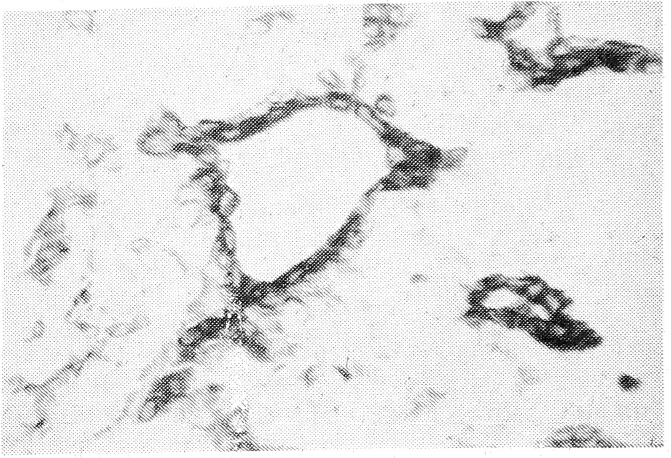

В нормальной слюнной железе эпителиальные клетки ацинусов и выводных протоков давали отрицательную реакцию с антителами к миозину, карбоангидразе III и полипептидам цитокератина № 17, при резко положительной реакции миоэпителиальных клеток указанных гистроструктур железы (рис. 1). Положительная реакция с МКАТ к кератину № 17 сохранялась в 50% клеток, примыкающих к железисто-протокоподобным структурам, и в единичных клетках хондро-миксоидных зон плеоморфной аденомы. Абсолютное большинство клеток указанных зон показывали экспрессию антител к миозину и карбоангидразе при люминесцентной микроскопии (рис. 2). Полипептиды цитокератина № 8 выявлены во всех железистых клетках ацинусов и междольковых выводных протоков, а цито- кератин № 18 был положительным лишь в клетках выводных протоков. В плеоморфной аденоме экспрессия указанных антител наблюдалась в эпителии железисто-протокоподобных структур и в меньшей степени — в клетках пролиферата (рис. 3).

Рис. 1. Иммунофлюоресцентное исследование нормальной слюнной железы. Свечение цитоплазмы миоэпителиальных клеток внутридолькового протока (антитела к карбоангидразе III. ×300).